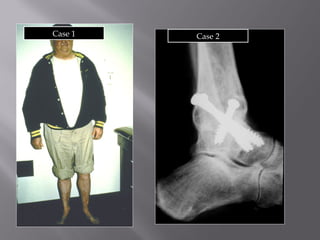

5 years - no pain

Case 1 ankle score 95

6.5 yrs - miserable -

Case 2 ankle score 45

Case 1 Case 2